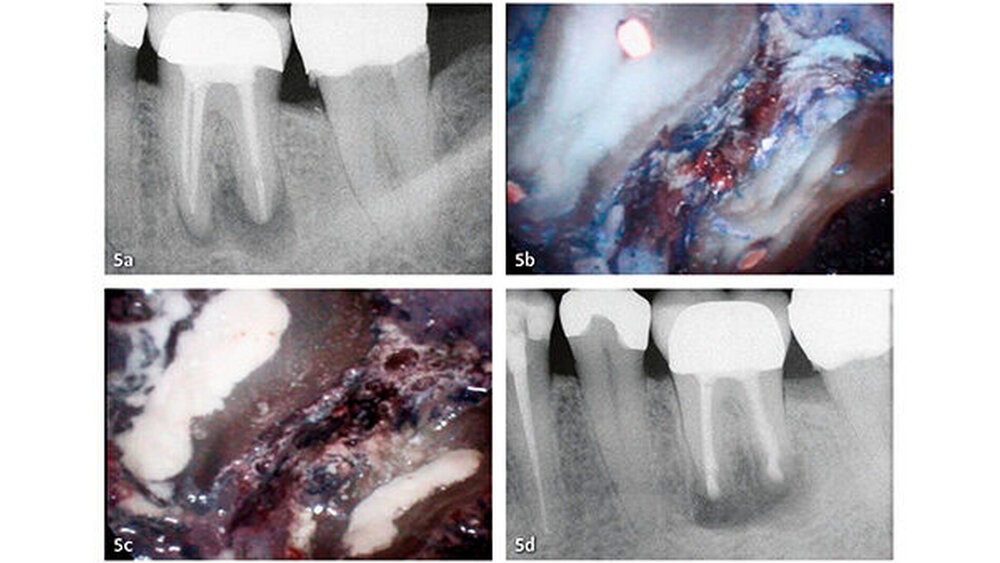

Klinische Studien

Die wesentlichen Daten von klinischen Studien über die Anwendung von MTA als retrogradem Füllmaterial sind in Tabelle III zusammengefasst. Die erste klinische Studie mit Auswertung der Erfolgsrate nach MTA-Anwendung in der apikalen Chirurgie wurde von Chong et al. (2003) publiziert - es war auch gleich die erste randomisierte Studie, welche MTA mit einem anderen retrograden Verschlusszement untersucht hat. Generell zeigen alle klinischen Studien sehr hohe Erfolgsraten für MTA in der apikalen Chirurgie (83,7% bis 96%). Die von uns 2014 publizierten Langzeitdaten (5 Jahre Beobachtungsdauer für alle behandelten Zähne) mit einer Erfolgsrate von 92,5% deuten auf eine sehr gute Stabilität und auf ein hohes Abdichtungsvermögen von MTA (von Arx et al. 2014) (Abb. 4 und 5).

Die Dokumentation der 10-Jahresdaten ist im Gange, und die bisherige Analyse deutet auf eine konstant hohe Erfolgsrate auch nach zehn Jahren (Abb. 6). Eine systematische Auswertung mit Meta-Analyse aller bis 2007 publizierten retrograden Füllmaterialien in Vergleichsstudien mit mindestens zwei getesteten Verschlussmaterialien ergab für MTA die höchste Wahrscheinlichkeit einer periapikalen Ausheilung (91,4%) (von Arx et al. 2010a).